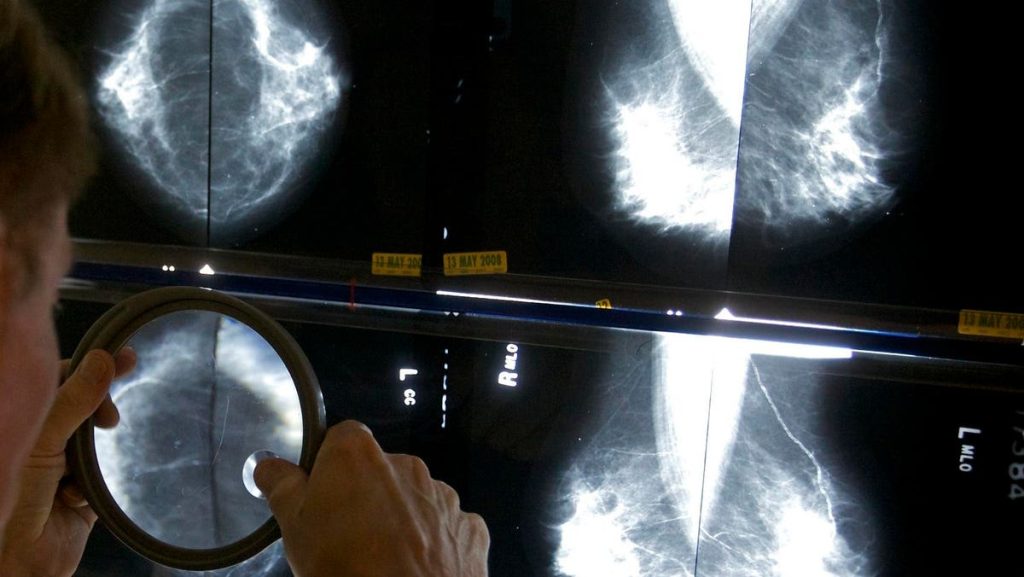

Can artificial intelligence (AI) help detect breast cancer? A new study out of Sweden has tentatively said: yes.

The study enrolled over 80,000 women in a clinical trial to ask this question. All 80,033 underwent mammography. Half of those mammograms were interpreted the standard way in Sweden, which is by two physicians. The other half had their mammograms read by a physician (or two physicians) who had an AI-supported analysis.

What’s an “AI-supported analysis?” That’s when the AI system reviewed the images of the mammogram first, then gave the images a score from 0-10. The image and the score then was reviewed by a radiologist (or two radiologists if the score was 10, the highest risk score).

The study found that AI-supported screening found 20% more cancers as compared to the standard review by physicians who did not use AI.

AI-supported screening did not increase the number of false positives, meaning it did incorrectly diagnose mammograms as abnormal.

The workload of radiologists was reduced by 44% when using AI. However, an important difference between the US and Sweden is: in the US, mammograms are only read by one physician, not two. So the benefit of saving time is, at baseline, less important in the US as compared to Sweden.

“These promising interim safety results should be used to inform new trials and program-based evaluations to address the pronounced radiologist shortage in many countries. But they are not enough on their own to confirm that AI is ready to be implemented in mammography screening,” cautions lead author Dr Kristina Lång from Lund University, Sweden, who spoke to The Lancet. “We still need to understand the implications on patients’ outcomes, especially whether combining radiologists’ expertise with AI can help detect interval cancers that are often missed by traditional screening, as well as the cost-effectiveness of the technology.”

Dr. Laurie Margolies MD, vice chair of breast imaging at the Icahn School of Medicine at Mount Sinai, NY, shared: “We have seen some women with a low AI score, turn out to have concerning findings diagnosed by the radiologist. AI is an important and helpful tool but it’s not a replacement for the physician’s review.” For example, AI can miss breast lymphoma, which looks very different from a typical breast cancer on a mammogram.